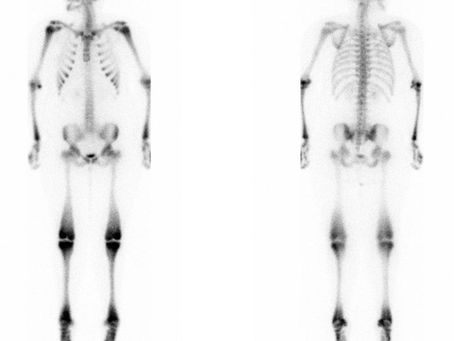

هشاشة العظام

هشاشه العظام أعتبرها عرض و ليس مرض التعامل مع هشاشه العظام كمرض هو طريقه تفكير سطحيه جدا والنتيجه مثل ما هو معروف المشكله لاتزال قائمه و...